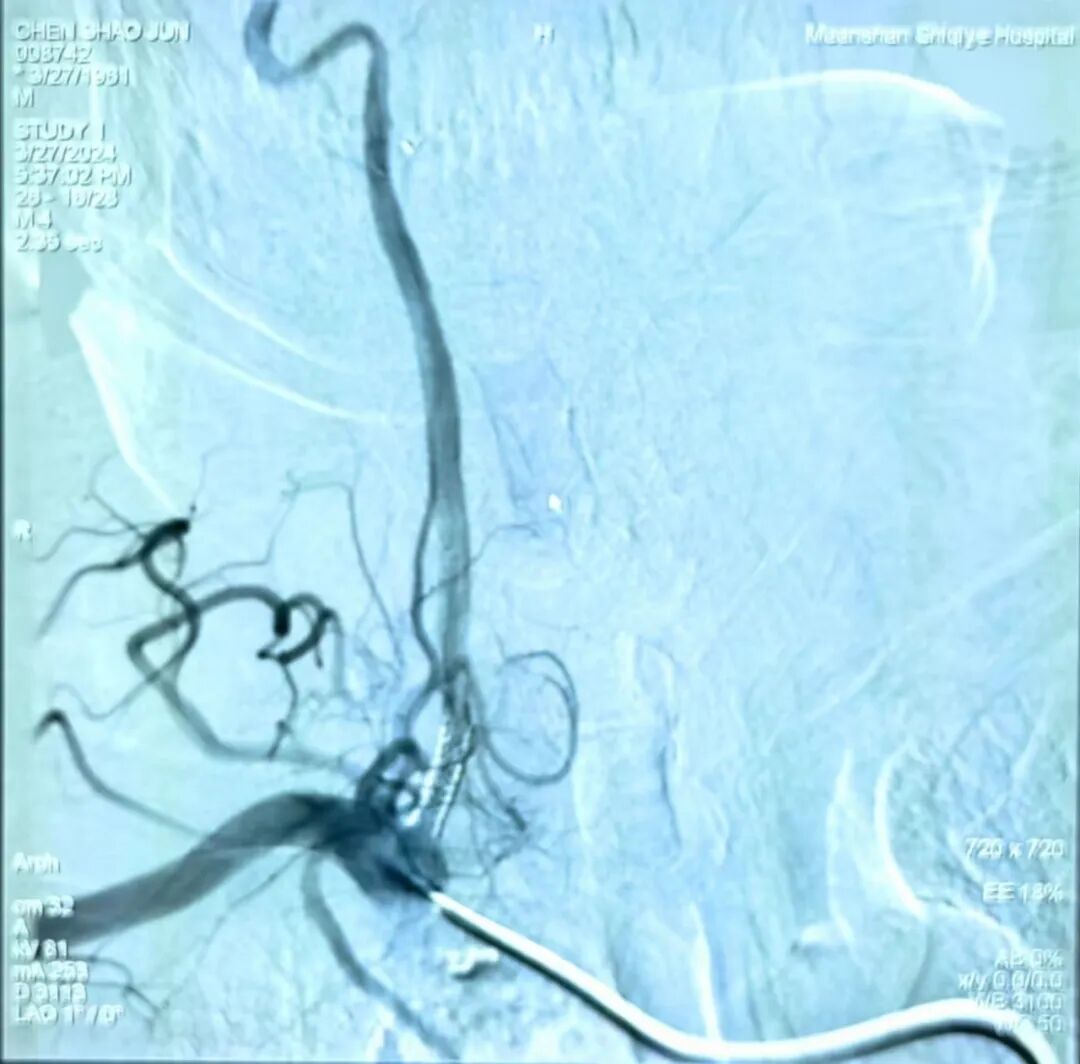

神经内科首例脑血管造影+经皮椎动脉支架植入术圆满成功

2024年3月27日下午四点,在导管室内,一场精心筹备的手术正悄然进行,我院神经内科成功开展了首例脑血管造影+经皮椎动脉支架植入术,标志着神经内科在脑血管病诊疗技术上迈出了坚实的一步,实现了里程碑式的飞跃。

本次神经内科首例脑血管造影+经皮椎动脉支架植入术,手术过程中,医生通过精细的操作,成功地将支架植入到患者狭窄的椎动脉处,恢复了血流通畅。同时,造影术的应用也帮助医生准确了解血管病变的位置和程度,为手术的成功提供了有力保障。手术进行得非常顺利,患者术后未发生并发症,生命体征稳定,术后恢复良好。这一成功案例不仅展现了神经内科医生高超的技术水平,也体现了神经内科在脑血管病介入治疗方面的综合实力。